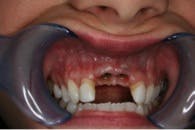

One year after the crowns were replaced, the teeth became mobile. The patient went in for an appointment and radiographs confirmed external root resorption had occured around the reimplanted teeth (refer to figure 3).

The root resorption in this case was most likely due to PDL damage. Treatment options were explained and the decision was made to extract the teeth and place dental implants. She was referred to a Mankato, Minnesota oral surgeon for the implants.